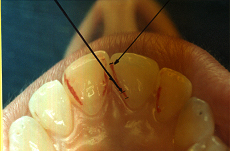

En ciertas áreas del saber humano, el lenguaje confuso o criptográfico Muchas son las técnicas elaboradas para lograr un desgaste selectivo, y numerosos autores han expuesto en su momento variadas formas de lograr una función oclusal fisiológica mediante el ajuste de la misma. Han pasado años desde entonces y, sin embargo, aún hoy, un altísimo porcentaje de profesionales “navega” por el mar de la confusión oclusal, dada la diversidad de conceptos y escuelas, sin lograr arribar a costa alguna donde poder anclar un conocimiento sólido sobre cómo tratar la oclusión Ya se esté realizando una simple obturación, endodoncia, incrustación, radectomía u ortodoncia, la lógica pocas veces, en la mayoría de los casos, vincula un tratamiento con otro, siendo el resultado final el mismo caos inicial; enmascarado por mucho tratamiento profesional. El ajuste oclusal es un medio inicial de proveer al sistema enfermo de: Dicha técnica, que puede ser terapéutica en sí misma; consta de dos etapas, a saber: 1) Ajuste Oclusal por Adición Mediante el estudio de la guía anterior, encargada de efectuar las Disclusiones durante las excursiones mandibulares, podremos observar si ésta es funcional o no. • Marcas de carácter continuo, si en ese recorrido se produce la Disclusión de los sectores posteriores y todo marcha correctamente. FIG 1-2 Si por el contrario observamos: • Marcas de carácter discontinuo, significa que dicha Disclusión se está efectuando por medio de una pieza dentaria posterior a la guía anterior. FIG 3-4-5 (FIGS. 3, 4 Y 5). En la figura 6 las flechas indican, en un caso clínico de análisis oclusal, la presencia de marcas discontinuas que indican Interferencias en Propulsiva. FIG 6-7 Y por último, si existieran: • Abrasiones de las áreas discluyentes en las áreas de diagnóstico de la guía anterior, deberemos aportar material a dicha zona para no permitir el choque lateral de las piezas posteriores (Ajuste Oclusal por Adición) En las imágenes 11 y 12 podemos observar la adición de composite en la punta de un canino derecho, previa la observación de la Faceta Parafuncional remarcada durante el análisis oclusal en el articulador. (FIGS. 8 A 12). 2) Ajuste oclusal por Sustracción o Desgaste Habiendo cumplido ya con la verificación de la funcionalidad de la Guía Anterior, comenzamos los desgastes en céntrica, a fin de lograr un único arco de cierre, guiado eficazmente por la Guía Anterior; es decir: la coincidencia entre Oclusión Habitual y Oclusión en Relación Céntrica. En este caso, intentar gastar dichos puntos, de ser posible sólo en las cúspides de corte o no fundamentales: • Crestas Triangulares Internas, Cúspides Vestíbulares Superiores • y un poco de las Crestas Triangulares Internas, Cúspides (FIGS. 13 A 16). Si la deflección es hacia el lado opuesto, se invierten los desgastes. En las migraciones hacia adelante, las únicas razones posibles están en los puntos estabilizadores (FIG. 17); es decir: -Vertientes Distales de los Rebordes Marginales, Triangulares (FIG 17) (FIG 18 A-B-C-D) Obsérvese cómo, en una boca prácticamente entera, comienzan a “desmoronarse” prismas adamantinos (FIG. 19), como consecuencia de un punto prematuro de contacto, ubicado en la posición de un estabilizador, que provoca la discrepancia horizontal postero-anterior causante de dicho efecto (FIG. 20). FIG 19-20 Dicho punto, será necesario ajustarlo antes de cualquier tratamiento en la zona ¿Cuáles serían las consecuencias si esos incisivos fueran implantados tal como es frecuente observar en múltiples congresos y cursos de implantología, donde el tema de la oclusión no es más que un cuadro polifacético y anecdótico? 14 15 16 17 Todo producto del adelantamiento mandibular Realizados ya los desgastes en céntrica, obteniendo de esta manera un único arco de cierre, es decir, oclusión en relación céntrica, debemos realizar el ajuste de las excéntricas, apoyando la acción de la guía anterior, para lo FIG 22 a. De un lado a otro de un mismo maxilar, la imagen es especular, o sea invertida. b. En hemimaxilares cruzados, la imagen es idéntica. Allí donde existan colisiones entre cúspides, se deberá crear un surco para que dicha cúspide antagonista migre a su través, tanto en el lado de no trabajo, como en el de trabajo y en el de propulsión. FIG 23 Es importante conservar esta parte del surco, ya que si no existieran, los contactos entre cúspides serían en superficie y no puntiformes (fig. 24). FIG 24 1. Obtener un único arco de cierre con coincidencia entre oclusión habitual y relación céntrica. 2. El cierre mandibular debe ser recibido sólo por la tabla premolar-molar. 3. Durante las excursiones funcionales es la guía anterior la que debe sufrir las fuerzas laterales. 4. De cumplirse estas dos premisas debemos obtener libertad de desplazamiento (no confundir con libertad en céntrica) a las piezas posteriores mediante la creación de surcos disclusivos. Examinadas ya las posibles migraciones mandibulares y los desgastes o aposiciones necesarios para poder ocluir en céntrica, es fundamental recordar que, previamente a todo tipo de ajuste, se ha hecho necesario ubicar a la mandíbula en relación céntrica. Para ello debemos utilizar el propio funcionalismo muscular 22 FIG 25 Y esto no significa otra cosa que: piezas dentarias estables en todos los planos del espacio, ATM centrada en la cavidad glenoidea, periodontos sin tensión, músculos en la dimensión de elongación adecuada para un fisiologismo Paz absoluta en la intimidad del Sistema Estomatognático. Y así, como corolario final, es posible establecer una regla de oro similar en importancia a la conocida formula: Forma = Función Ésta es: FIG 26 FUNDAMENTOS NEUROFISIOLÓGICOS DEL REGISTRO DE OCLUSIÓN EN RELACIÓN CÉNTRICA ( ORC) MEDIANTE EL USO DE LAMINILLAS DE LONG CUADRO

En la figura 7, se muestran la Disclusión Inicial (durante el transcurso de la cual deben separarse por completo los sectores posteriores –flecha izquierda–, y la Disclusión Final de recorrido mucho más largo –flecha derecha–.